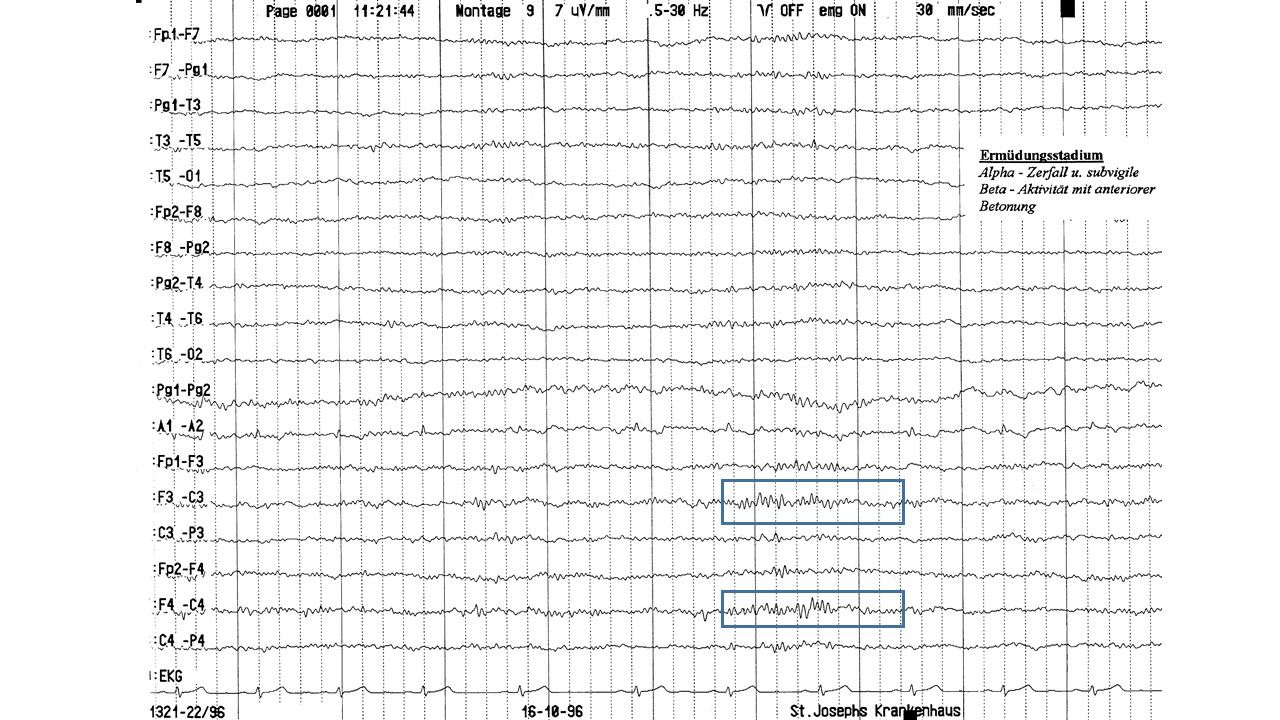

EEG-Seminar II | 28.59 zurück | weiter